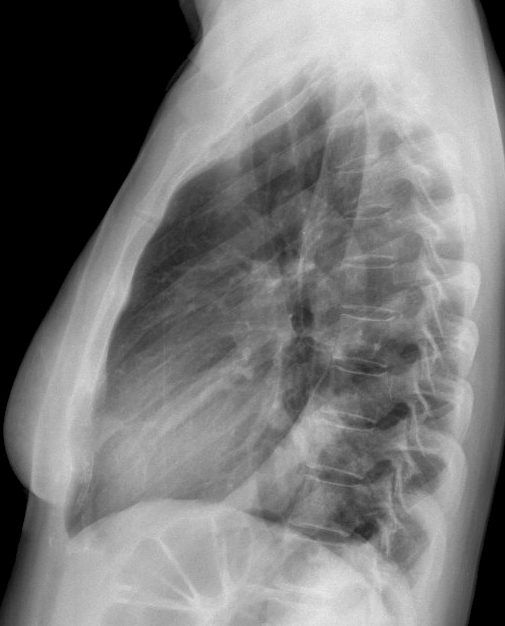

Case 12 antmed LLL pneum Lat

Date: 04/17/2005